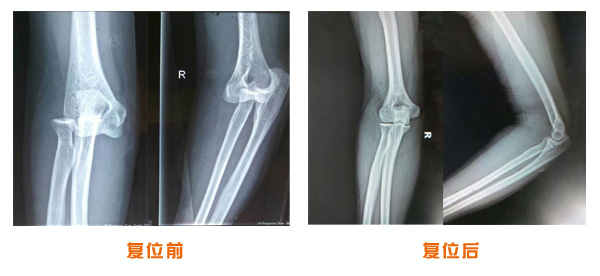

尺橈骨骨折治療前后